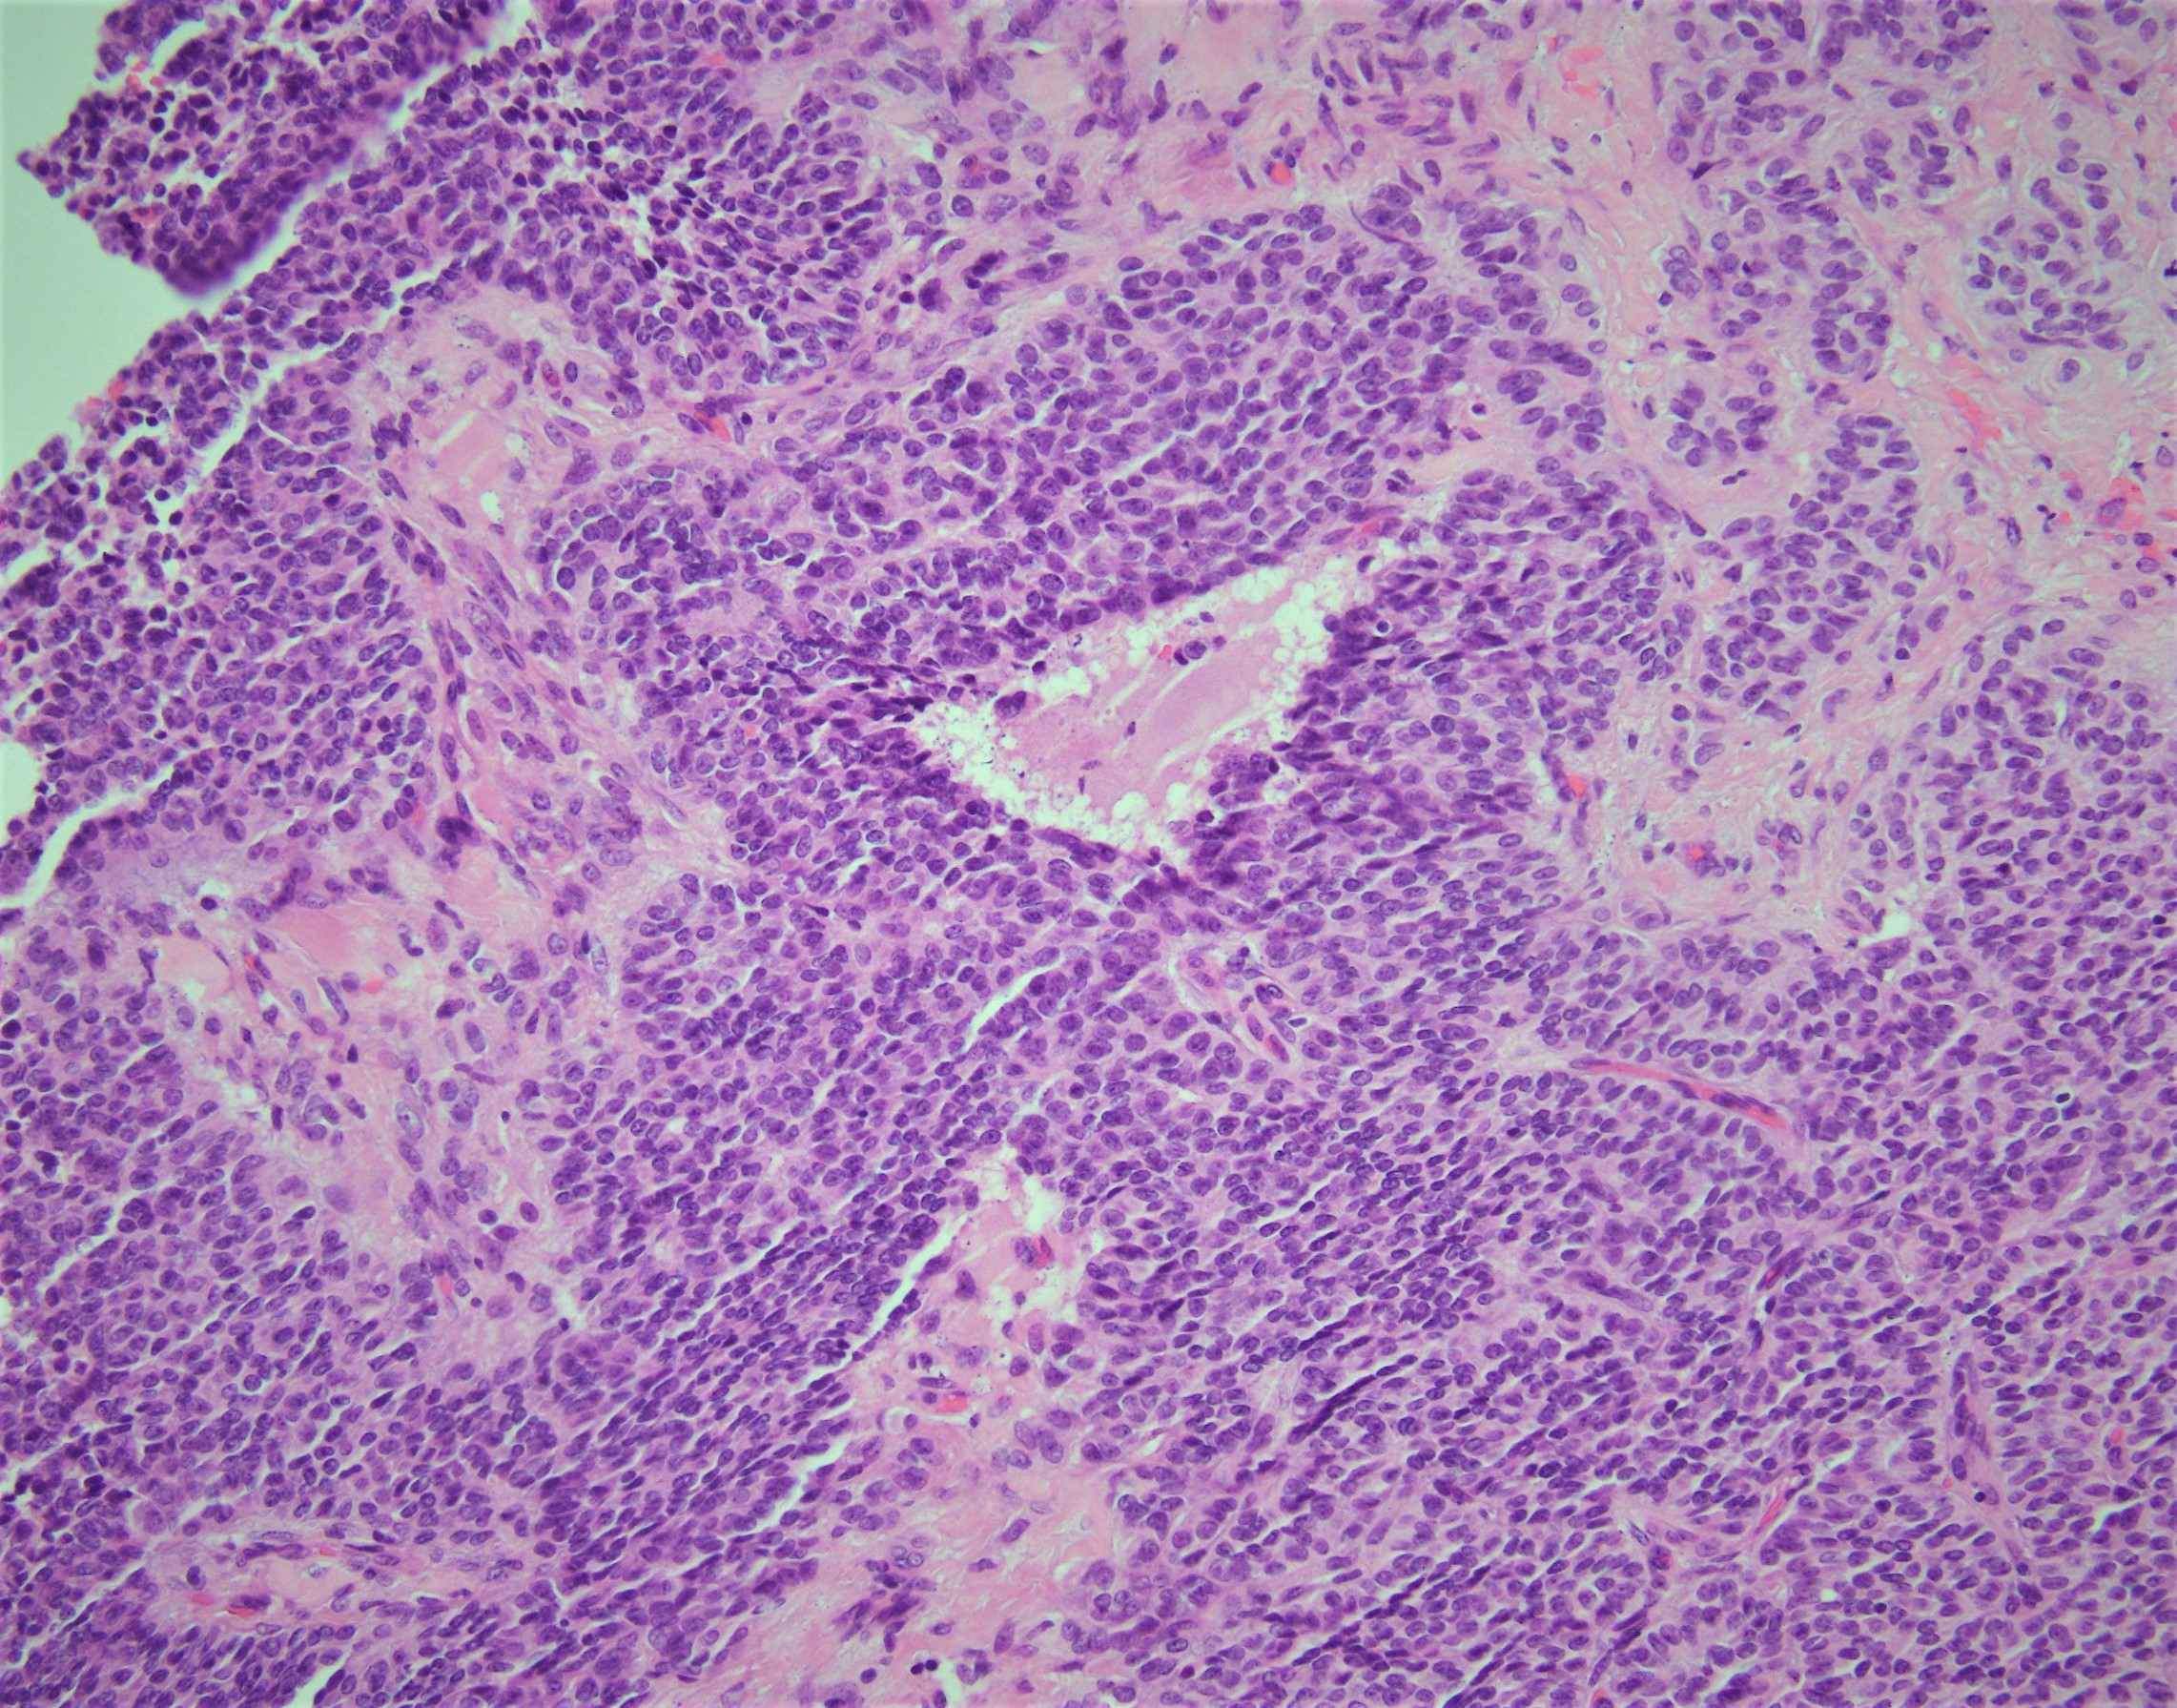

Answer: D. Granulosa cell tumor, adult type.

Histologically, the neoplastic cells comprising these neoplasms show scant cytoplasm and oval to angulated nuclei with prominent nuclear grooves such as in this case.  Architecturally, these neoplasms can present in a wide variety of histologic patterns.

AGCTs are typically reactive for inhibin and calretinin and are negative for EMA.  Additionally, these neoplasms were shown to have a single-point mutation in the FOXL2 gene.